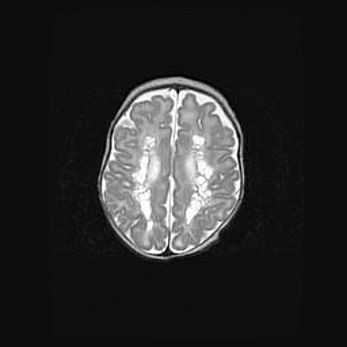

Церебральная ишемия II.

Возраст: 7 дней

Вес: 3350 г

Пол: женский

Окружность головы: 35 см

Срок гестации: 39 недель

Ишемия головного мозга – это состояние, которое развивается в ответ на кислородное голодание вследствие недостаточного мозгового кровообращения. У новорожденных она является следствием дефицита кислорода, что ведет к метаболическим расстройствам различной степени тяжести в тканях головного мозга, в том числе к развитию коагуляционных некрозов и гибели нейронов.